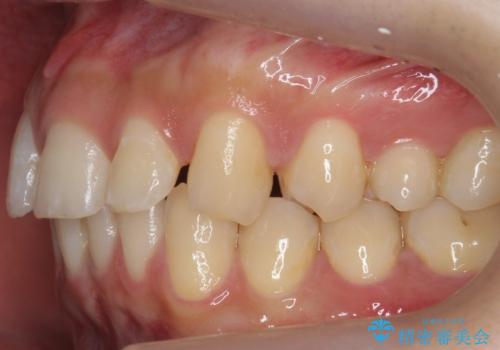

患者様の歯は咬耗といって削れて短くなっていたため、セラミックでかぶせると隙間をうめるため横長の歯になりそうでした。術後の見た目は矯正の方が自然にみえるとお伝えしました。

料金としてはセラミックで上下ともかぶせた場合、矯正治療以上にかかってしまう可能性をお伝えしました。

ただし、上に隙間が余っている状態ですと、ただ閉じようとしても上の前歯が中に入らないと隙間が閉じないため、下の歯の位置によっては隙間が閉じ切れなくなります。

その場合は下の歯を上の前歯から離す方向に圧下したりする動きが必要になり、全体矯正が必要になります。

また、隙間を閉じる方法は矯正が一番いいわけではなく、矯正治療、セラミック治療それぞれ特徴があります。